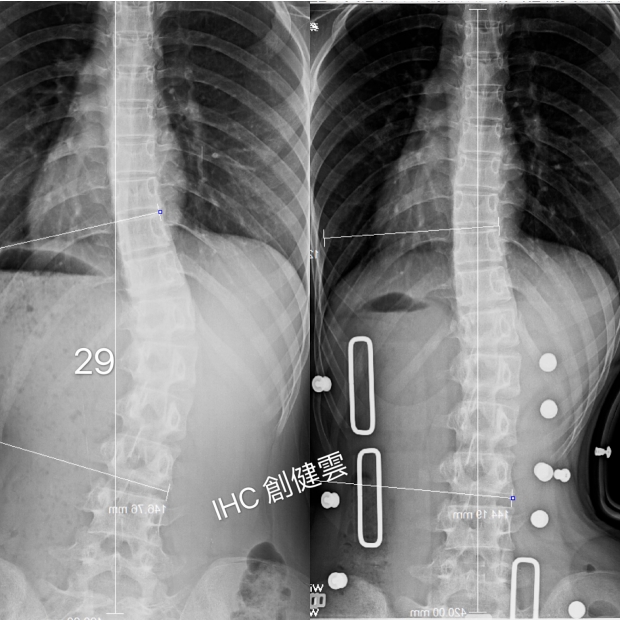

14歲脊椎側彎女孩

胸腰彎29度